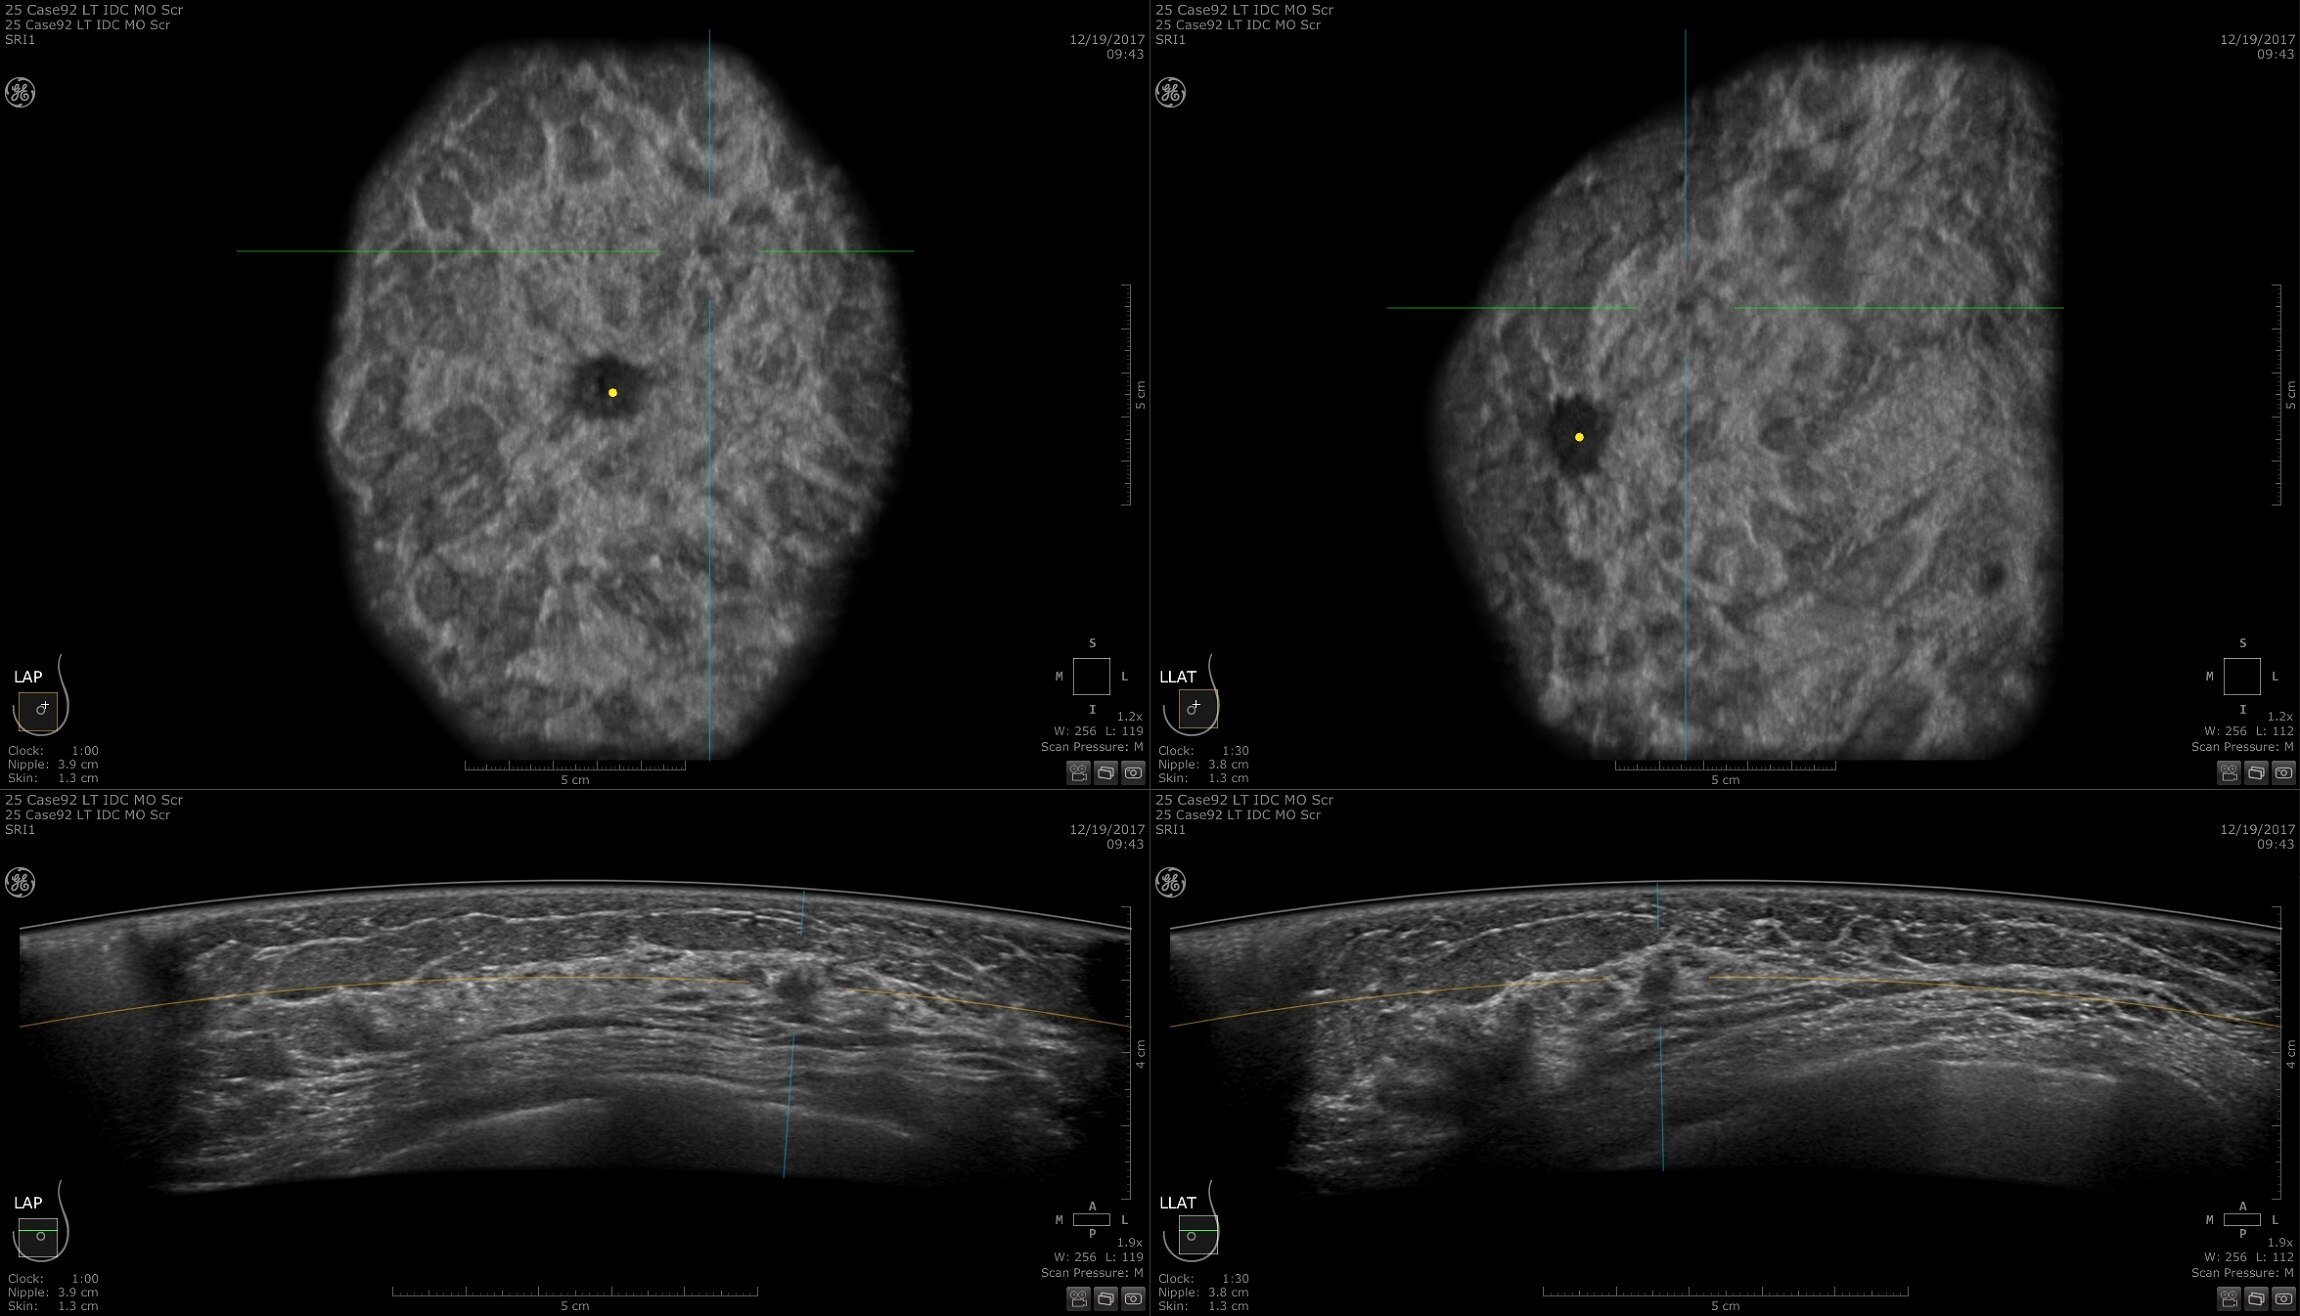

Dense breast tissue and cancer appear white on a mammogram, potentially camouflaging small cancers. Invenia ABUS 2.0, is specifically designed to help clinicians find cancers that may be hidden on mammography1,2.

Lesion characterization for confident staging in dense breasts

Invenia ABUS 2.0 uses the latest ultrasound innovations and AI based solutions to help improve precise diagnosis and elevate clinical confidence.